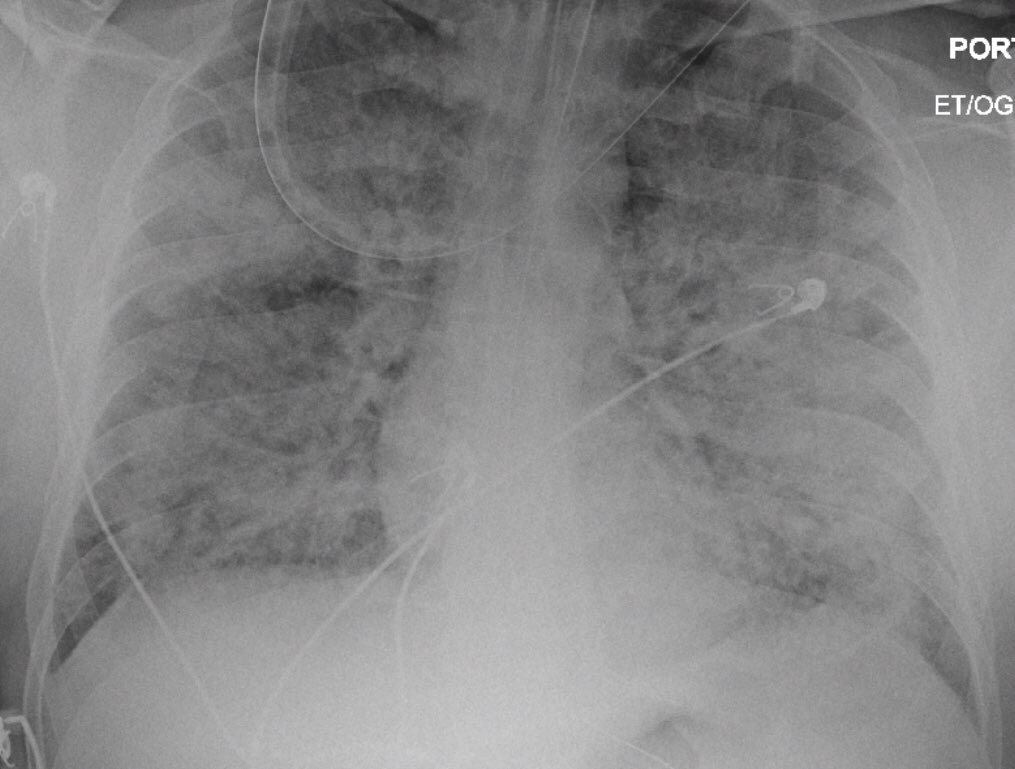

- هل تعتقد ان ARDS او متلازمة الضائقة التنفسية الحادة خلال جائحة #كورونا هي :

2- restrictive:

-وهي الصورة الإكلينيكية في متلازمة ARDS حيث تُغلق الحويصلات الهوائية بسبب تراكم السوائل بسبب إصابة الأوعية الدموية ( مثل اَي حالة التهاب )، مما يجعل عملية تبادل الغازات والاستفادة من الاوكسجين محدودة جدا.

- يحتاج المريض المساعدة في اعادة فتح الحويصلات.

- نحتاج زيادة اوكسجين للمريض ولكن الاوكسجين لن يستطيع الوصول للحويصلة ما دام هناك سوائل.

يقوم الجهاز التنفسي الصناعي على وضع ضغط على الحويصلة الهوائية مما يساعد على فتحها مما يساعد على الاستفادة من الاوكسجين.

- عندما تقل مرونه نسيج الرئة في حالة ARDS بسبب وجود السوائل ف يتطلب ضغط عالي اكبر .